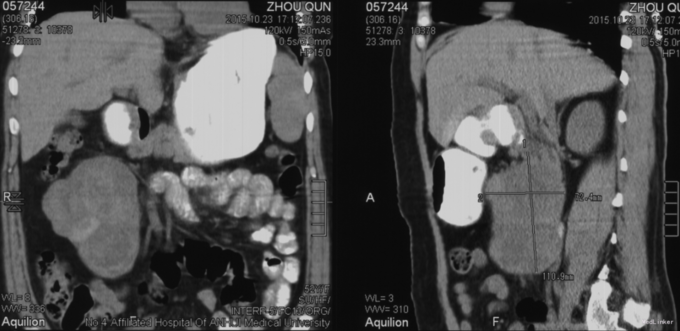

诊断:胰腺实性假乳头状肿瘤。 治疗:排除手术禁忌证后行胰头肿物切除术;术中探查肿块主体位于腹膜后,肿块外侧界位于十二指肠降部内侧,下届位于脐下4cm,内界位于腹主动脉前方,上界位胰头部,肿块活动度尚可,从十二指肠降部侧壁打开后腹膜,分离胰头和十二指肠,打开侧腹膜,将右半结肠推向左侧,见肿块包膜完整,沿肿块包膜分离结肠系膜与周围疏松组织,kocher法将胰头及肿块翻起至腹主动脉左侧,进一步沿肿块包膜分离,发现肿物上缘同胰头部胰腺包膜延续,范围约1.5*2cm,考虑肿瘤来源于胰头部,外生性生长,遂沿肿瘤基底部使用电刀完整切除肿瘤,靠近胰头小网膜处放置引流管一根。术后给予抗炎、制酸、抑酶等治疗,术后查引流管淀粉酶升高,改双腔冲洗管引流5天,淀粉酶指标降低,改单套管后,患者病情稳定,出院修养。10天后回院未见明显引流液,拔出引流管,无不适。

目前随访中。 实性假乳头状肿瘤是一种胰腺外分泌肿瘤,多发于女性,发病率低且术前诊断较为困难。此患者因为肿瘤大,位置相对表浅,可以术前行穿刺活检明确病理。改患者比较幸运,肿瘤仅同一线包膜有少许粘连,只需完整切除肿瘤即可,预后一般较好。